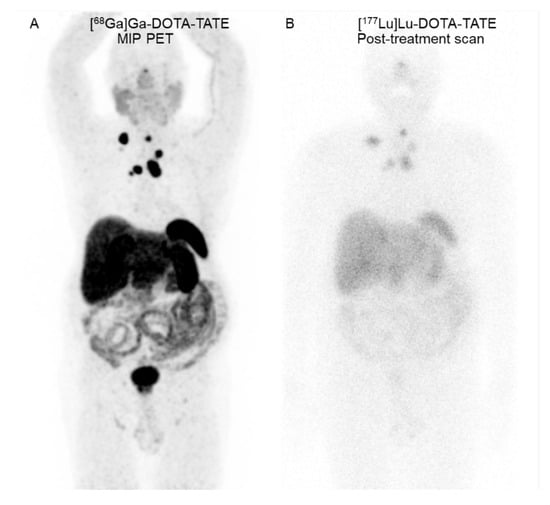

After 4 years, local recurrence and the progression of nodal metastases were found. He underwent salvage neck dissection. Post-operative [68Ga]Ga-DOTA-TATE positron emission tomography/computed tomography (PET/CT) revealed multiple SSTR-positive residual tumors in the pre-tracheal region and nodal metastases in the bilateral supraclavicular, mediastinal, and right internal mammary regions (Figure 1). An additional three cycles of [177Lu]Lu-DOTA-TATE (7400 MBq per cycle) separated by 8-week intervals were completed.

Figure 1. A 66-year-old man with metastatic medullary thyroid cancer. (A) Coronal maximum-intensity projection (MIP) [68Ga]Ga-DOTA-TATE PET image reveals SSTR-positive lesions in the residual tumors at the pre-tracheal region and neck, mediastinal, and right internal mammary metastatic lymph nodes. (B) Seven-day [177Lu]Lu-DOTA-TATE post-treatment scan reveals [177Lu]Lu-DOTA-TATE uptake in all known SSTR-positive residual tumors and nodal metastases.